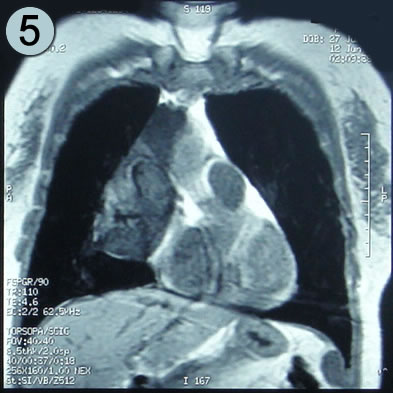

Corte Coronal en secuencia T1

La lesión con forma de botella, el cuello de la lesión naciendo en el seno de la arteria pulmonar, su parte mas amplia paracardiaca derecha no llega al ángulo pleuropericardico.

El seno cardiofrenico esta libre y sin derrame pleural.